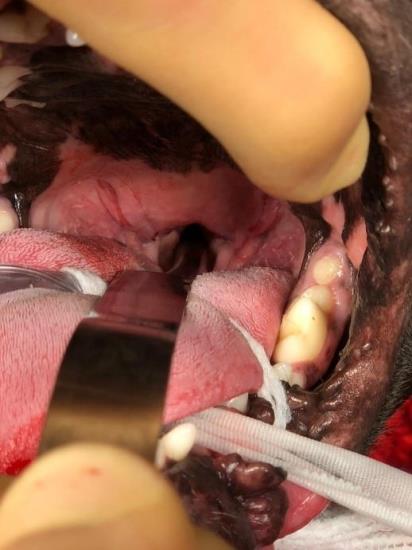

Surgery involves removing the end of the soft palate making it shorter (picture 1a+b), this allows air to pass through the pharynx more freely. If the animal is in a more advanced stage of the syndrome the laryngeal saccules are also removed to stop them collapsing into the larynx.

Picture 1a: Brachycephalic dog with long soft palate before surgery

Picture 1b: Brachycephalic dog after the soft palate has been surgically resected